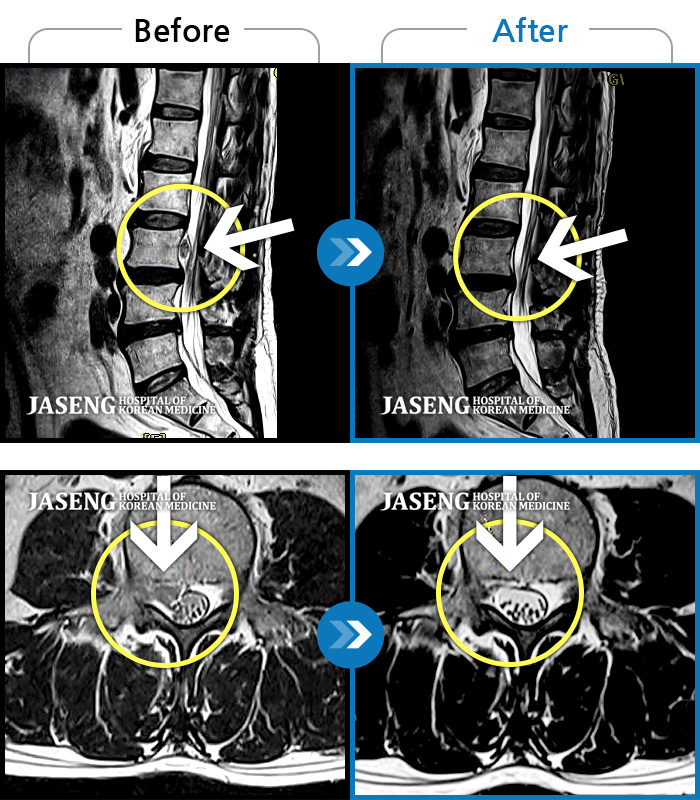

허리디스크

광주 · 이일석 원장

허리부터 골반이 묵직하고 뻐근한 통증, 우측 허벅지까지 이어지는 저림 증상으로 내원하셨습니다.

촬영시기

2025.01.20 ~ 2025.10.25

2025.10.30